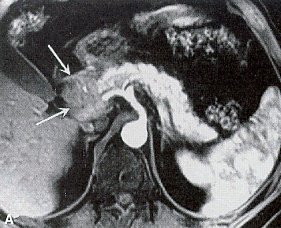

Arterial-phase gadolinium-enhanced MRI showing a pancreatic head mass (arrows)

Of the 16 patients who had a detectable lesion by MRI, 14 had an intraductal papillary mucinous neoplasia and two patients had pancreatic ductal adenocarcinoma. One patient had a synchronous intraductal papillary mucinous neoplasia and pancreatic ductal adenocarcinoma.